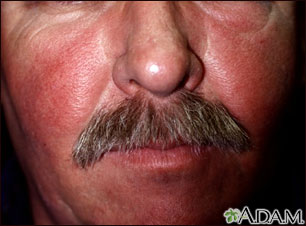

Seborrheic dermatitis is a rash that appears in patches of redness and scaling around the eyebrows, eyelids, mouth, nose, trunk, and behind the ears. If it happens on your scalp, it is called dandruff in adults and cradle cap in infants.

Age, stress, fatigue, weather extremes, oily skin, infrequent shampooing, and alcohol-based lotions aggravate this harmless but bothersome condition.